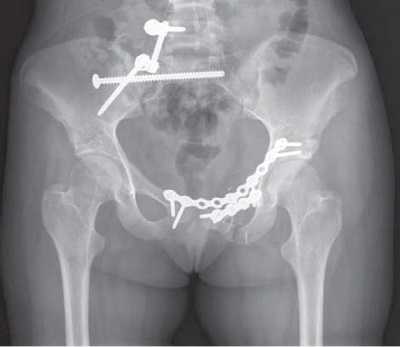

Открытая репозиция и внутренняя фиксация. В ходе операции костные фрагменты в первую очередь возвращаются в нормальное анатомическое положение (репонируются). Для удержания фрагментов в этом положении до наступления сращения используются металлические пластины и винты.

В данном случае для стабилизации перелома костей таза использованы пластины и винты.